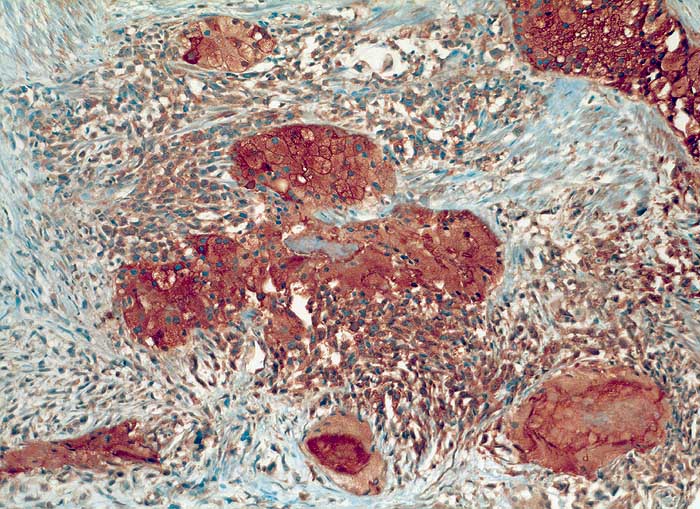

Sowohl die klarzellige als auch die sarkomatoide Tumorkomponente sind stark PSAP positiv.

Bei den immunhistochemischen Untersuchungen sind die epithelial differenzierten Tumoranteile positiv für den Epithelmarker Lu-5 und für die prostataspezifischen Marker PSA und PSAP. Die sarkomatös differenzierten Anteile sind dagegen Lu-5 negativ, zeigen aber ganz herdförmig eine schwache, aber eindeutige Positivität für PSAP (prostataspezifische saure Phosphatase). Die sarkomatösen Anteile sind ausserdem stark positiv für Vimentin und S-100. Die S-100-Positivität beweist zusammen mit der herdförmigen Ausbildung von chondroider Matrix und dem ausgedehnt myxoiden Hintergrund eine chondrosarkomatöse Differenzierung. Die myogenen Marker Actin, SMA und Desmin sind dagegen negativ bei positiver interner Kontrolle von glatten Muskelfaserbündeln und Gefässen. Der Proliferationsmarker Ki-67 wird in ca. 90% der sarkomatös differenzierten Tumorzellen, dagegen nur etwa in ca. 5% der epithelial differenzierten Anteile exprimiert.

Zusammengefasst handelt es sich hier um einen aussergewöhnlichen und seltenen Fall eines metaplastischen Karzinoms mit heterologen Anteilen (Chondrosarkom). Diese Tumoren machen lediglich ca. 0,1% aller Prostatakarzinome aus. Wie bei diesem Patienten, entwickeln sich etwa die Hälfte dieser Tumoren mit sarkomatöser Differenzierung aus einem gewöhnlichen Adenokarzinom. Die herdförmige Positivität der sarkomatösen Anteile für PSAP deutet auch hier darauf hin, dass diese durch Transformation des Adenokarzinoms entstanden sind. Einige Autoren bevorzugen deshalb auch den Begriff "metaplastisches Karzinom". Es ist denkbar, dass eine allenfalls vorausgegangene Strahlen- oder Hormontherapie bei dieser Transformation eine Rolle gespielt hat. Es handelt sich in der Regel um hoch aggressive Tumoren mit einer ungünstigen Prognose, wofür hier auch die ausserordentlich hohe proliferative Aktivität der sarkomatösen Tumoranteile spricht.